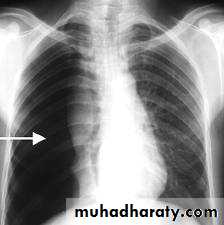

• CXR: Spontaneous pneumothorax is usually confirmed by chest x-ray ..

1. Expiratory films are better at demarcating the pneumothorax pleural line.2. Films should be done with patient standing, not supine.